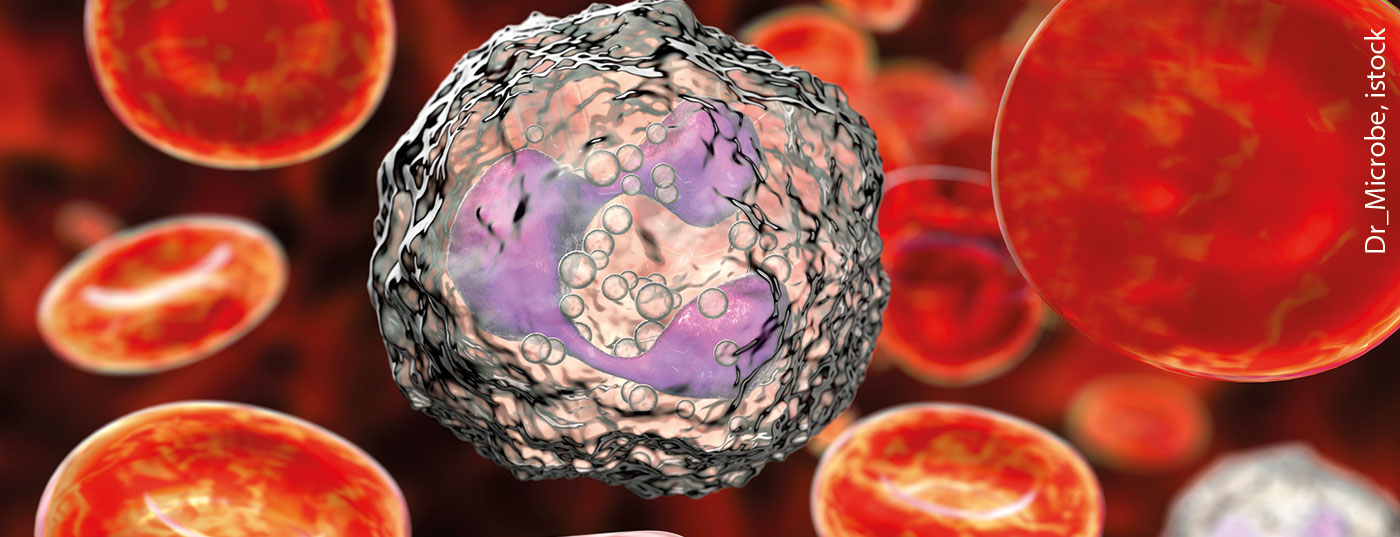

Die Neutropenie ist als eigenständiges Krankheitsbild, aber auch als Begleiterscheinung vieler Erkrankungen und als unerwünschte Arzneimittelwirkung ein häufiger Gast in der Praxis. Die damit einhergehende Infektanfälligkeit kann in vielen Fällen eine Herausforderung darstellen. Ein gutes Management beugt gefährlichen Konsequenzen vor.